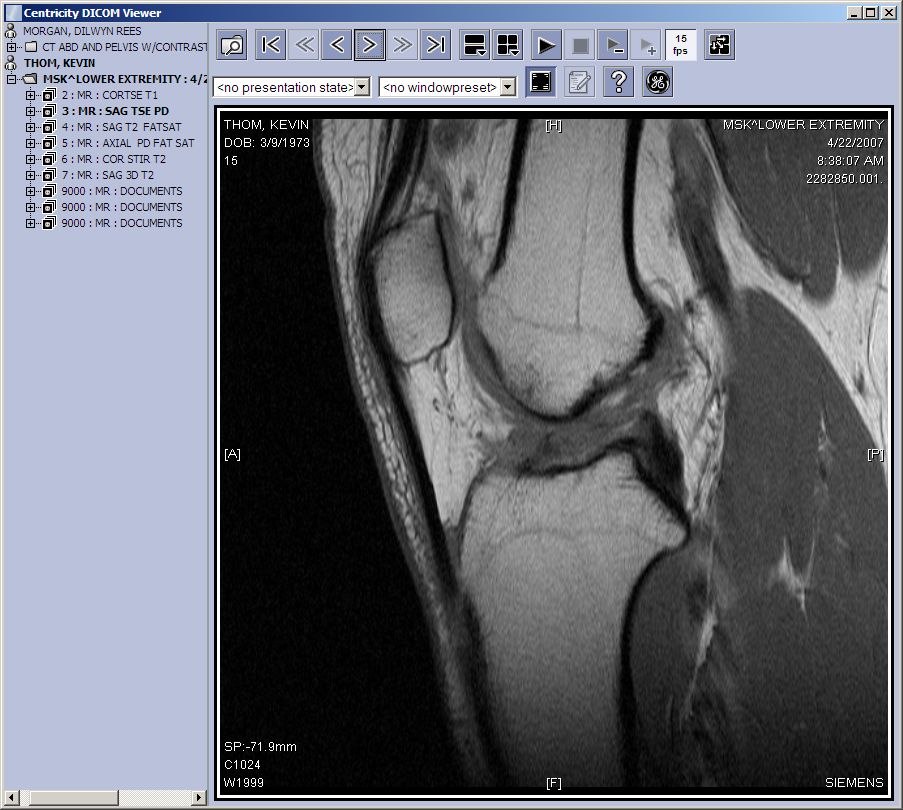

So I had my appointment with the sports medicine specialist today. Before I got there, I went to the hospital to pick up my MRI scans on CD. The disk is pretty cool. It runs an application that lets you step through all the “slices” of the MRI like a movie. There’s no doubt about it. My ACL is wrecked, and I’ve got a torn miniscus too. I think you can see the damage in this picture.

It’s a slice, side view. You can see where the two leg bones connect at the knee. The bones are the light grey phallic looking things from the top and bottom. The famous Thom calf muscle is darker grey, bottom right. The knee cap (patella) is the rectangle sort of in the top left. You should be able to see the ligament as a dark line connecting the two leg bones. Mine has given up and let go. Well, not so much “given up” as much as “wrenched from its moorings with a rather vile popping sound.”